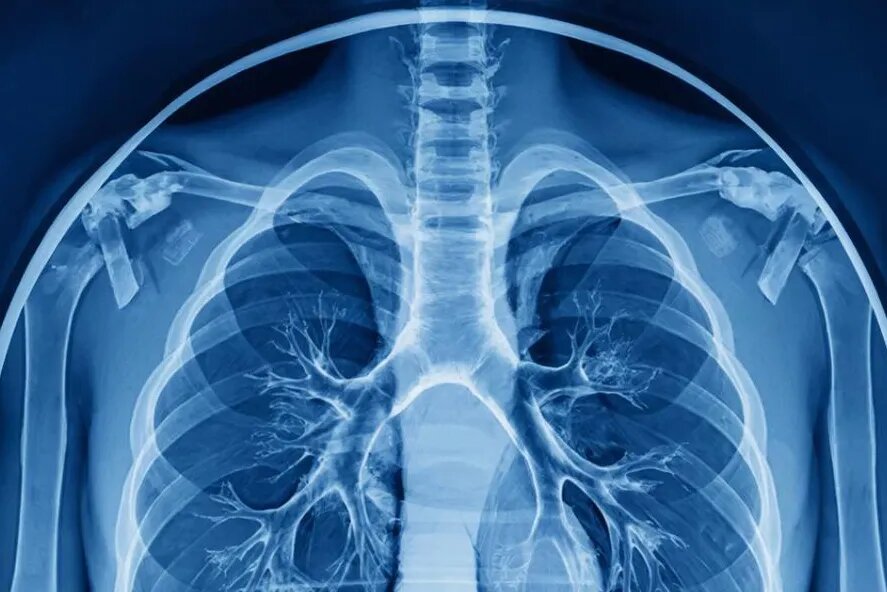

Специалисты Сеченовского университета совместно со специалистами «РТК-Радиология» разработали программный модуль на основе искусственного интеллекта. Он предназначен для планирования операций на органах грудной клетки. Об этом сообщил ТАСС со ссылкой на пресс-службу университета.

Модуль анализирует результаты компьютерной томографии и автоматически выполняет сегментацию лёгких, бронхиального, артериального и венозного деревьев. А также выявляет и локализует новообразования. Вооружившись интерактивными инструментами, хирург может оценить последствия потенциального удаления той или иной лёгочной структуры у пациента.

Директор Института персонализированной онкологии Сеченовского университета Марина Секачева рассказала, что новый модуль позволяет перейти от визуальной оценки к количественному анализу анатомии конкретного пациента и прогнозированию последствий операции. Это позволит сделать хирургические решения обоснованными.

По словам директора Клиники госпитальной хирургии Сеченовского Университета Евгения Тарабрина, хирургу критически важно еще до операции видеть полную анатомическую картину. Он должен знать точное местоположение опухоли, а также топографию сосудов и бронхов.

«Такой подход позволяет свести к минимуму объём резекции, снизить риски интра- и послеоперационных осложнений и сделать исход более предсказуемым», – сказал Тарабрин.